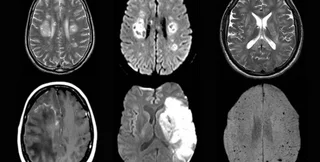

Фото: UCL

Они изучили протекание болезни у 43 человек в возрасте от 16 до 85 лет. У 10 из них была выявлена временная дисфункция мозга, а у 12 — его воспаления, некоторые из которых являлись острым диссеминированным энцефаломиелитом. Также наблюдались другие серьезные повреждения, например инсульты.